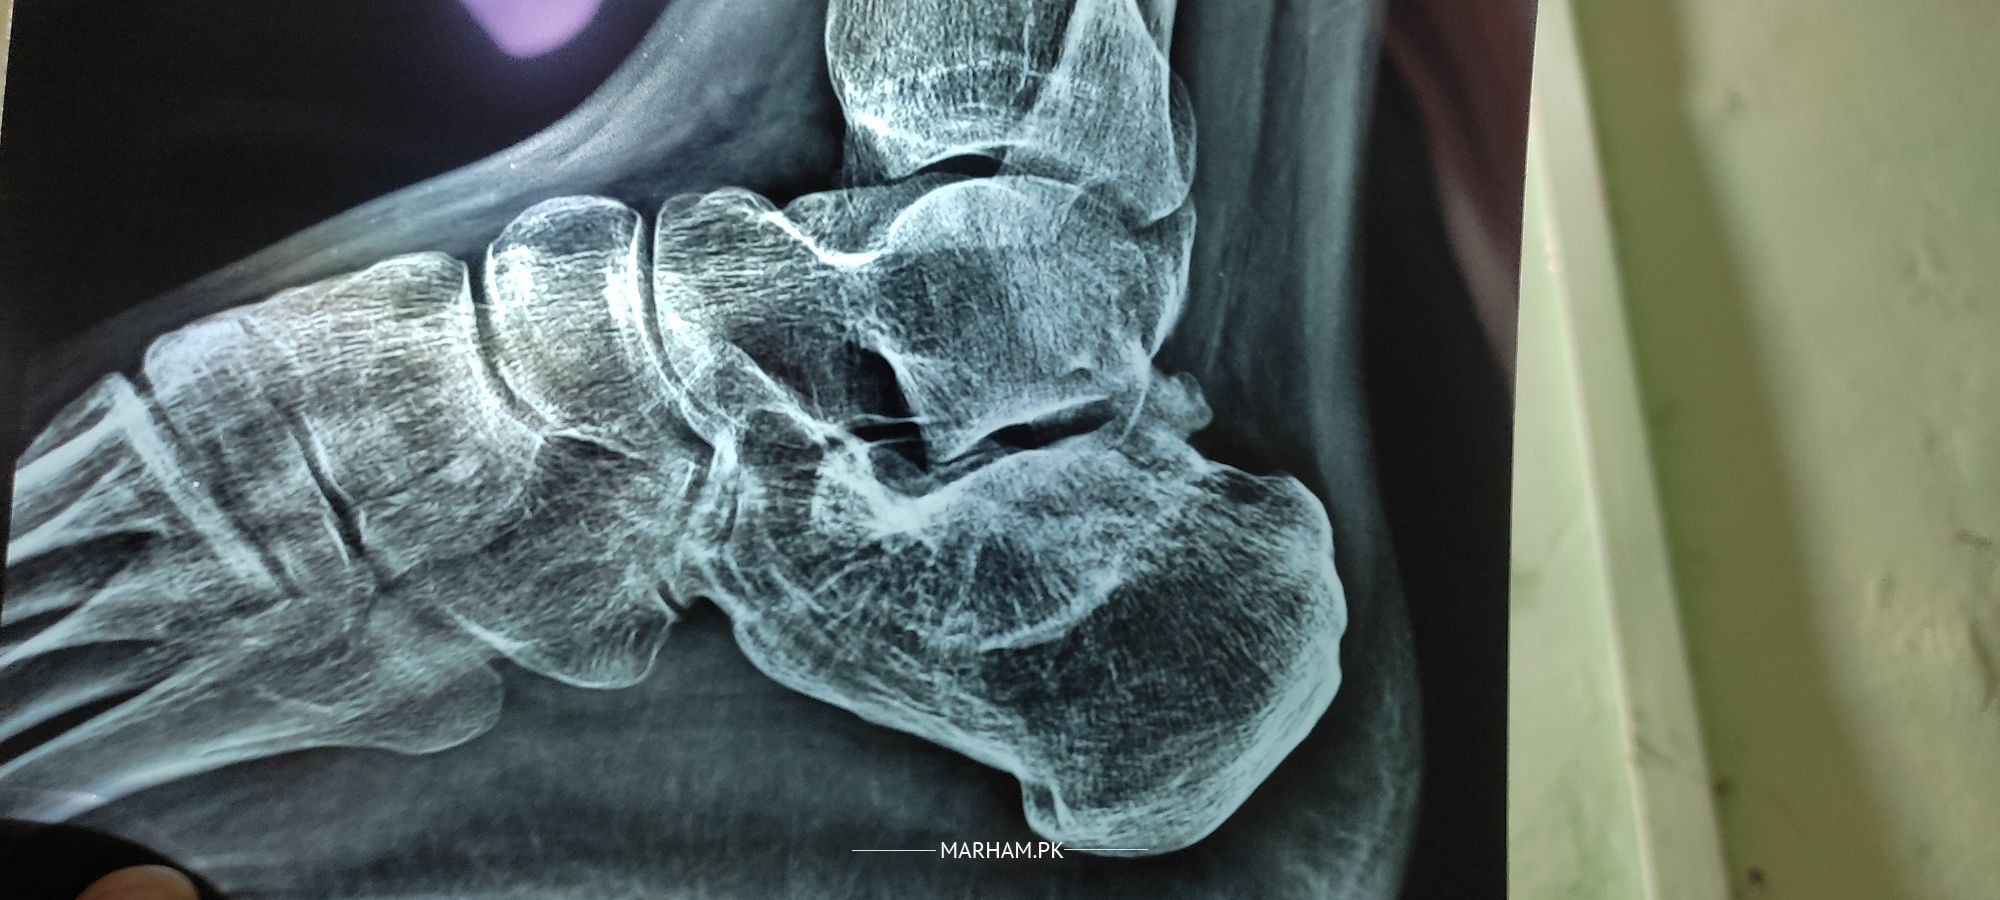

My Calcaneus bone was fractured in has been five years. It was healed but pain remains around the calcaneus and on the joint. I feel a little pain while walking and more pain when I walk for a long time and it's hard to run fast. I have taken medicines for muscle relaxers and pain relievers but after stopping pain starts again. What is the issue, is this arthritis or bone has not healed properly? Is there a need for surgery to make bone plain? Or it can be treated with medicines. I want to give a direct service commission in the army. Am I unfit for an army or should I give. Please suggest.

Attach Photo here: